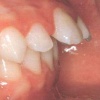

Turritavad ülemised lõikehambad

Ülemised eesmised hambad võivad olla liigselt ettepoole kaldunud mitmel põhjusel. - Hammaste huule poole kaldumine võib olla funktsionaalne ehk tingitud valedest harjumustest (suuhingamine, infantiilne neelamine), - kahjulikest harjumustest (pöidla, sõrme,...